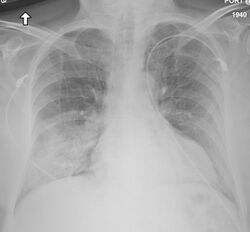

Medical imaging

Chest X-ray of a case of MERS

Chest X-ray findings tend to show bilateral patchy infiltrates consistent with viral pneumonitis and acute respiratory distress syndrome (ARDS). Lower lobes tend to be more involved. CT scans show interstitial infiltrates.[29]